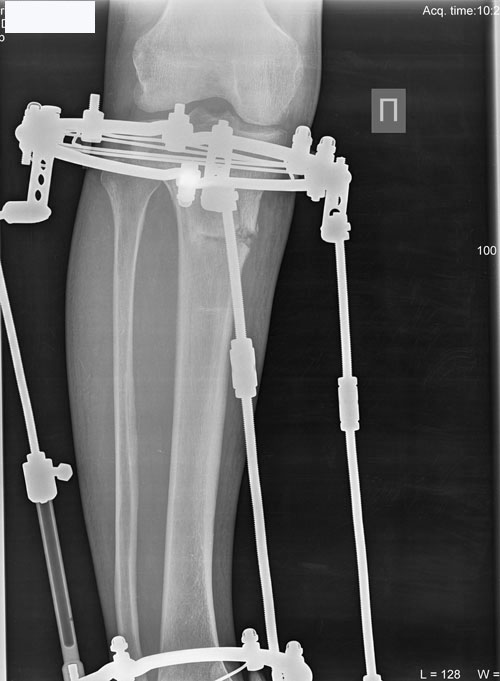

Рентген в 56 дней.

Сращение идёт отлично!

Л1.jpg

Л2.jpg